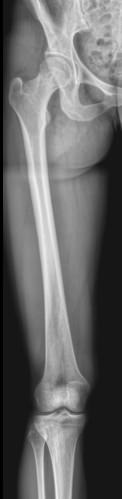

Обследование бедренной кости чаще всего выполняют рентгеновским методом. Это неинвазивный, безболезненный, высокоинформативный и доступный способ получения информации о состоянии и структуре костной ткани. Проходя через тело, рентгеновское излучение больше всего задерживается в самых плотных образования – костных, поэтому на классическом негативном снимке их изображения самые светлые. Патологические изменения, развивающихся здесь, также ясно видны. При их выявлении врач принимает решение о дополнительных видах диагностики и выбирает способы лечения.

• Состояние костной ткани и надкостницы: участки гнойного воспаления, разрежения, размягчения, деструкции, склерозирования, развития опухоли и кистозных образований;

• Изменения в мягких тканях: обызвествление, воспаление, опухоль;

• Целостность кости: свежие переломы, костные мозоли, ложные суставы.В заключении врач описывает преимущественно патологические изменения или пишет, что таких не обнаружено.